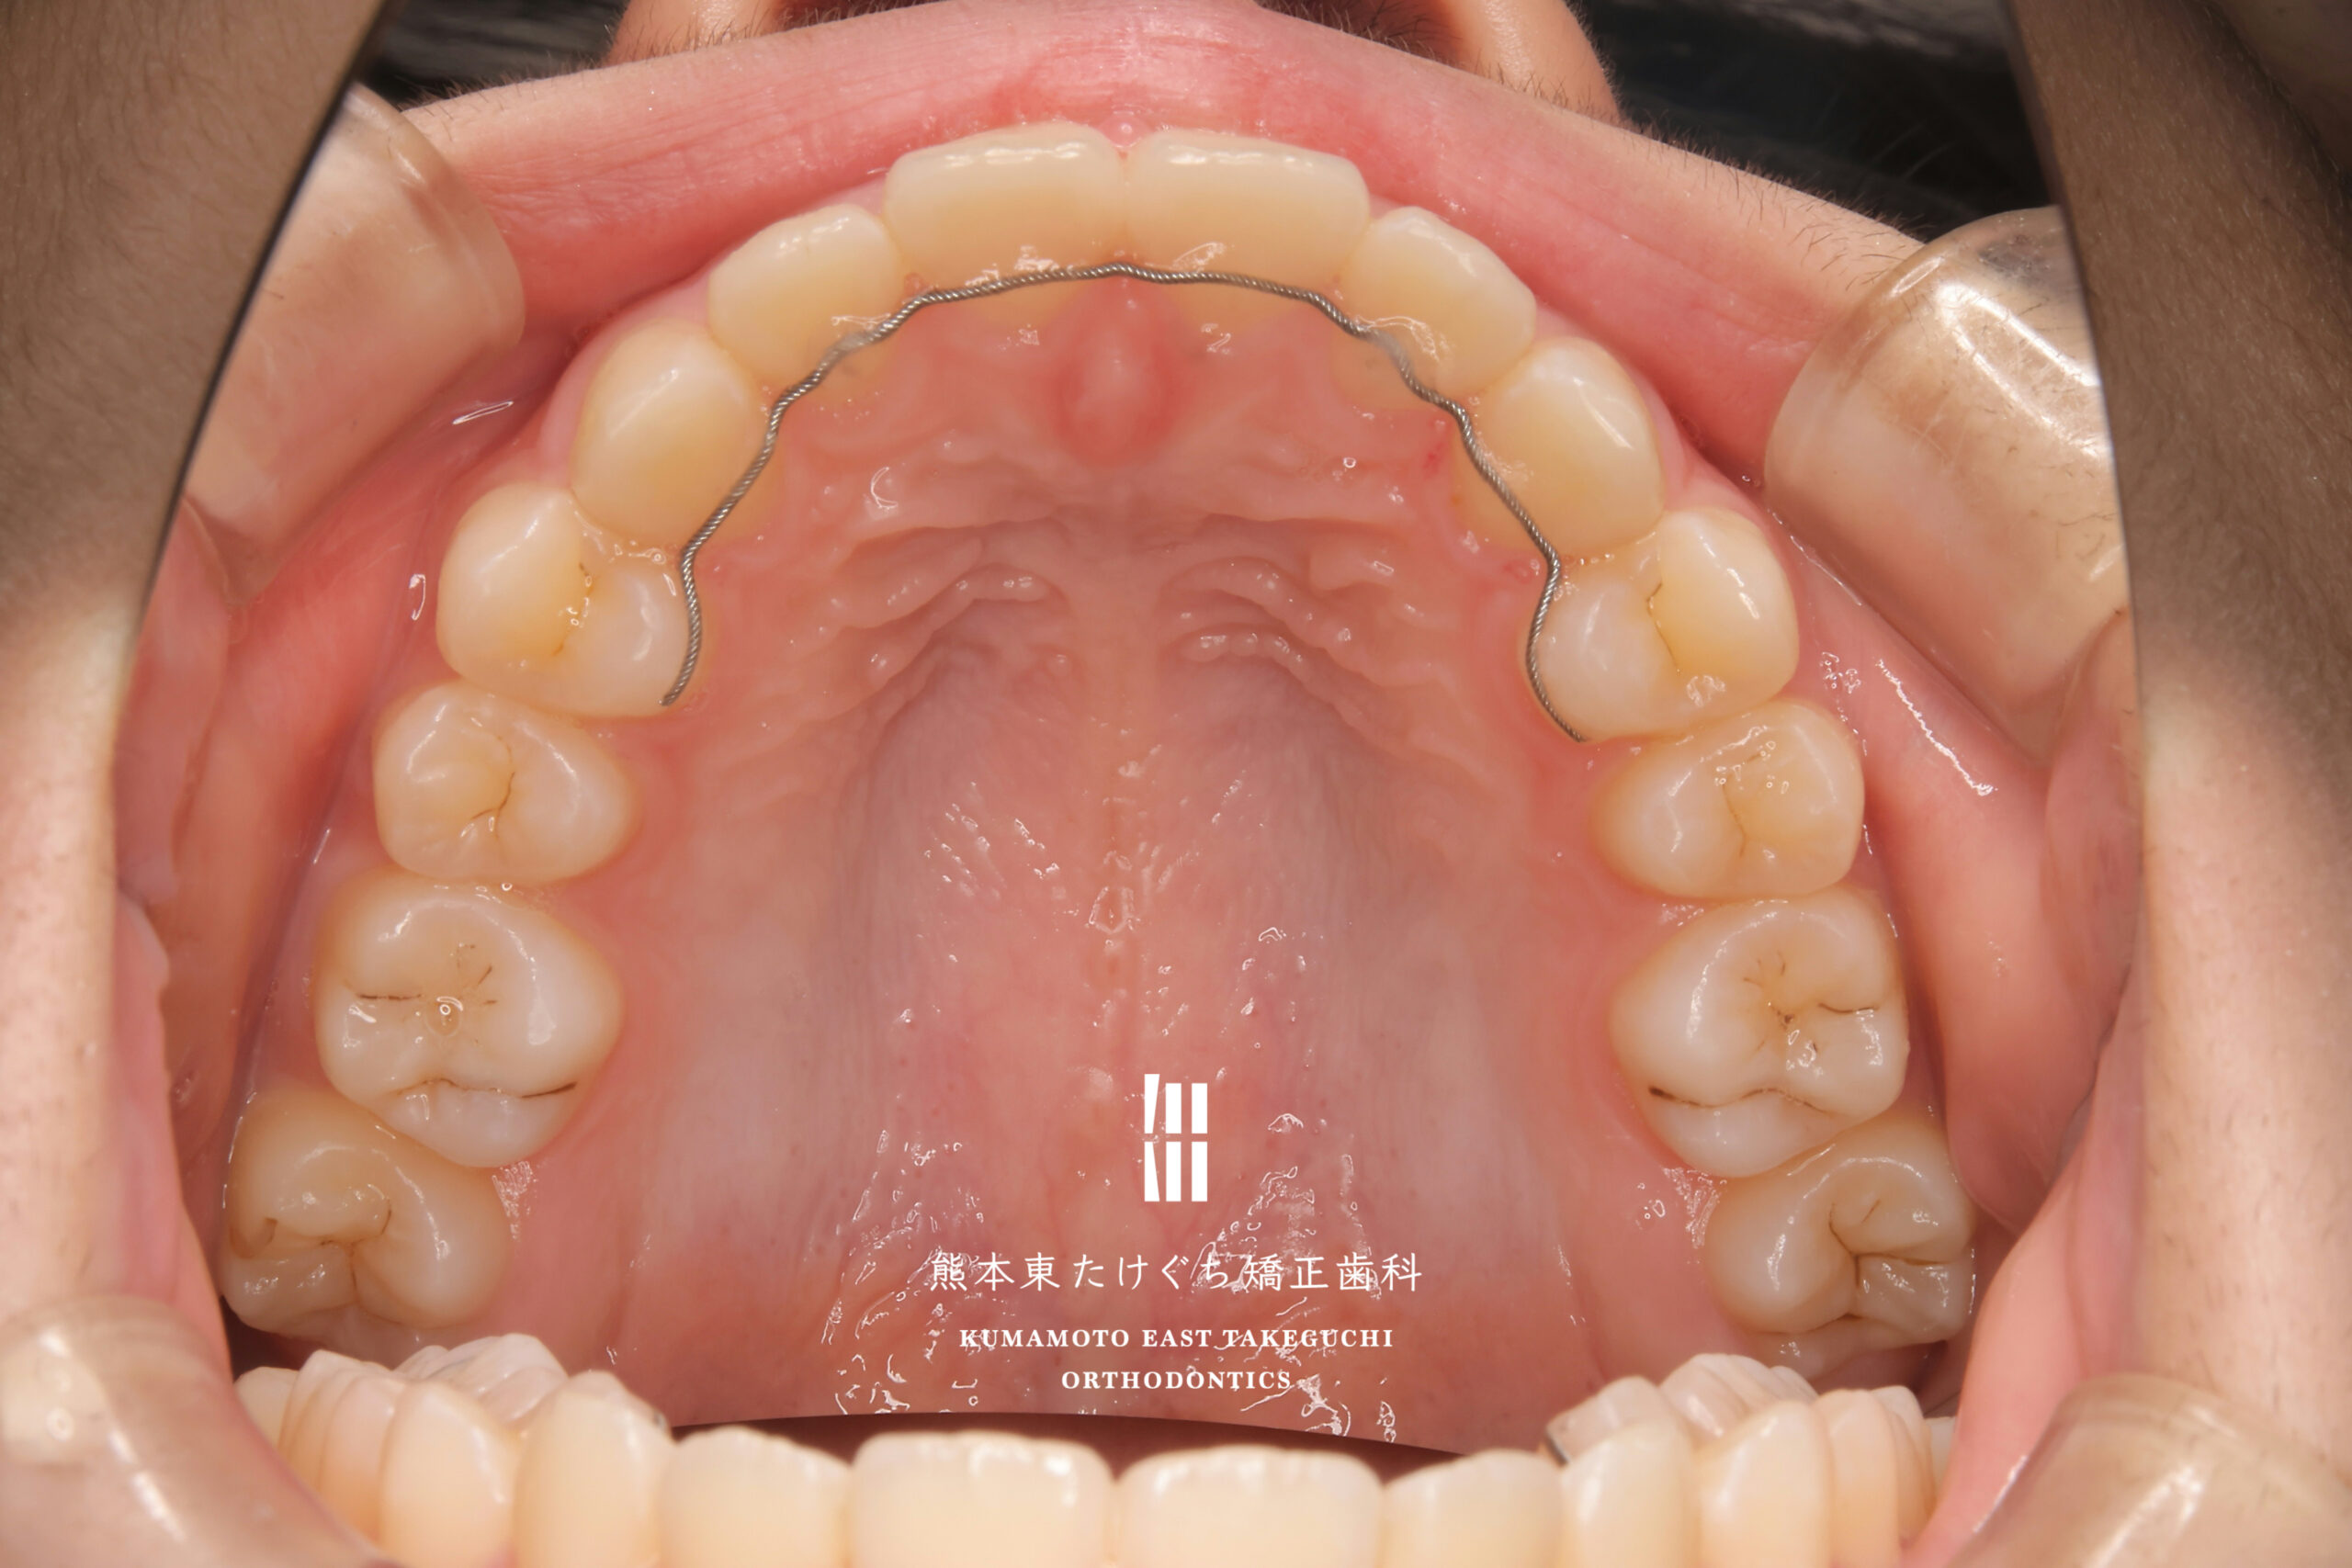

9歳女児 小児矯正 すきっ歯 かみ合わせが深い 出っ歯

治療内容 正中離開および過蓋咬合を伴う上顎前突を改善するため、取り外し式の矯正装置 BJA(バイト・ジャンピング・アプライアンス)と、部分的固定式ワイヤー装置を用いて治療しました。